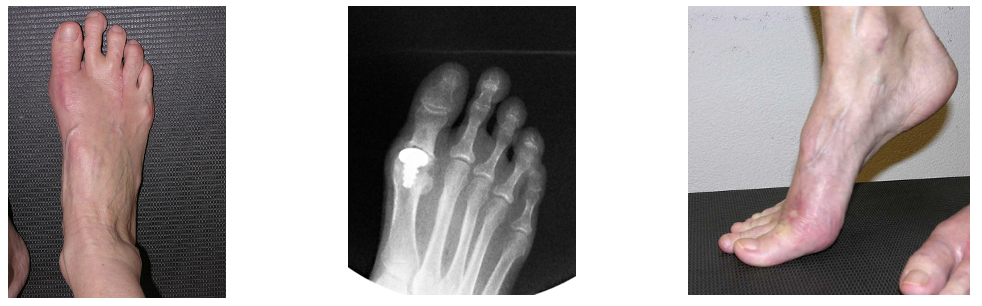

Die neuere Variante, als kompletter Gelenkersatz des Grosszehengrundgelenkes, die Toe Motion Prothese links, rechts das postoperative Röntgenbild.

Versteifung des GZG

Die Versteifung des Grosszehengrundgelenkes zählt zu den nicht gelenkerhaltenden Operationen. Die Versteifung wird als Arthrodese bezeichnet und gilt in der aktuellen Literatur weiter als Goldstandrad für die operative Therapie des Hallux rigidus. Die Ergebnisse der Literatur zeigen konstant zufriedenstellende und reproduzierbare Ergebnisse i.S. der Schmerzreduktion und hoher Patientezufriedenheit mit operativ relativ geringem Aufwand. Für die Versteifung des Grosszehengrundgelenkes stehen verschiedene operative Methoden zur Verfügung. Eine gängige und relativ einfache Operationstechnik ist die gekreuzte Schraubenarthrodese wie im unteren Röntgenbild dargestellt.

Gekreuzte Schraubenarthrodese zur Versteifung des Grosszehengrundgelenkes